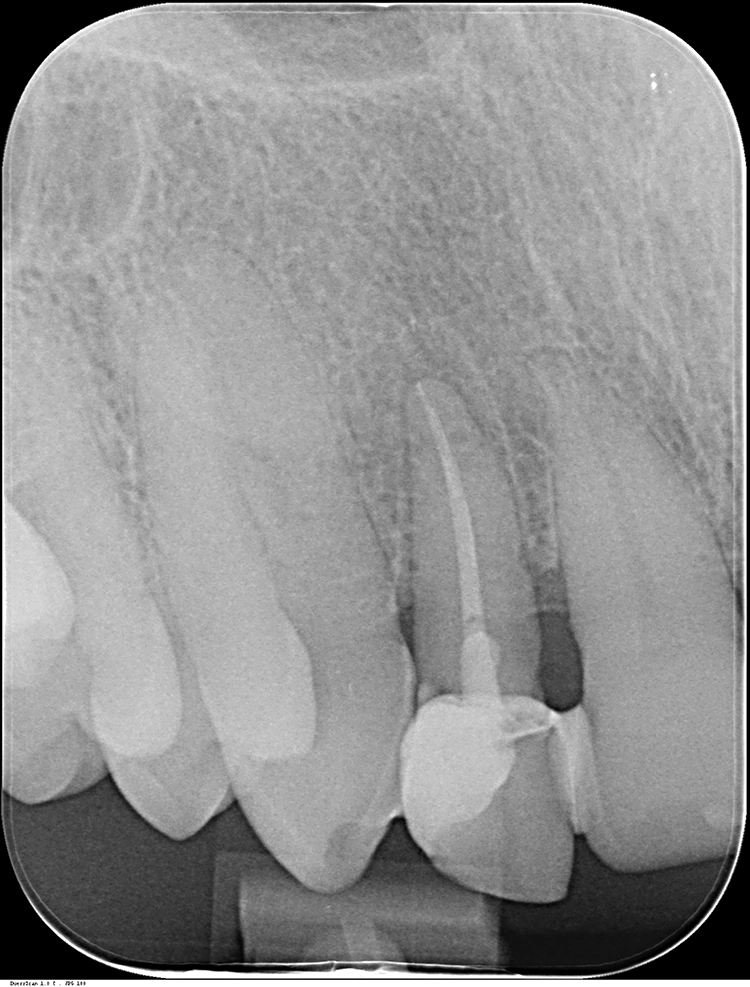

Zu unserem Ausgangsbefund zählt die sechs Punkt-Taschenmessung, die Vitalität und Perkussionsprobe sowie ein Röntgenbild. Besonders wichtig ist in diesem Zusammenhang auch die genaue Anamnese des Patienten.

Dr. Blume

Deutlich auffallend und für die Patientin sehr wichtig war die anatomisch individuelle Zahnstellung des Zahnes 11. Um dem Wunsch der Patientin auf eine für ihr Umfeld unauffällige Behandlung gerecht zu werden, entschieden wir uns gemeinsam für eine Sofortimplantation mit einer provisorischen Sofortversorgung des Implantates. Kein Provisorium kommt der Natur so nah wie die Natur selbst und daher planten wir die Umarbeitung der Zahnkrone 11.